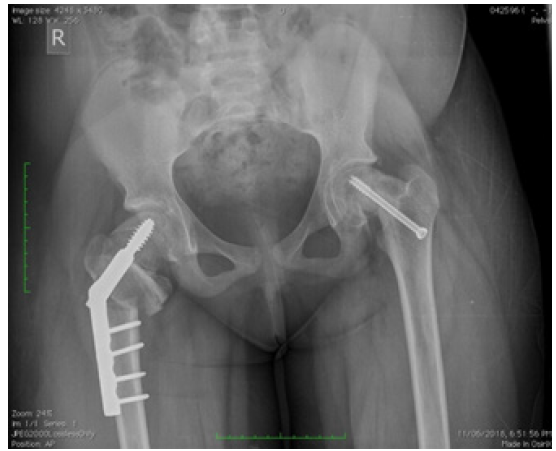

6 hips of 8 (75%) had open reduction and subcapital osteotomies while 2 had open reduction and subtrochanteric osteotomies. All subcapital osteotomies were fixed with 6.5mm cannulated cancellous screws while the subtrochanteric were fixed with dynamic hip screws. All patients with unilateral SCFE had bilaterally similar hip ROM at the time of last review. One patient had prophylactic contralateral pinning.

4 hips (50%) had complications; these included secondary osteoarthritis, coxa varus with LLD, delayed union and screw cutout requiring removal and re-fixation, affecting 1 hip each. There were no cases of AVN or chondrolysis complicating surgery. Mean follow-up duration for all patients was 22 months (range of 8-48 months) (Figure 1).